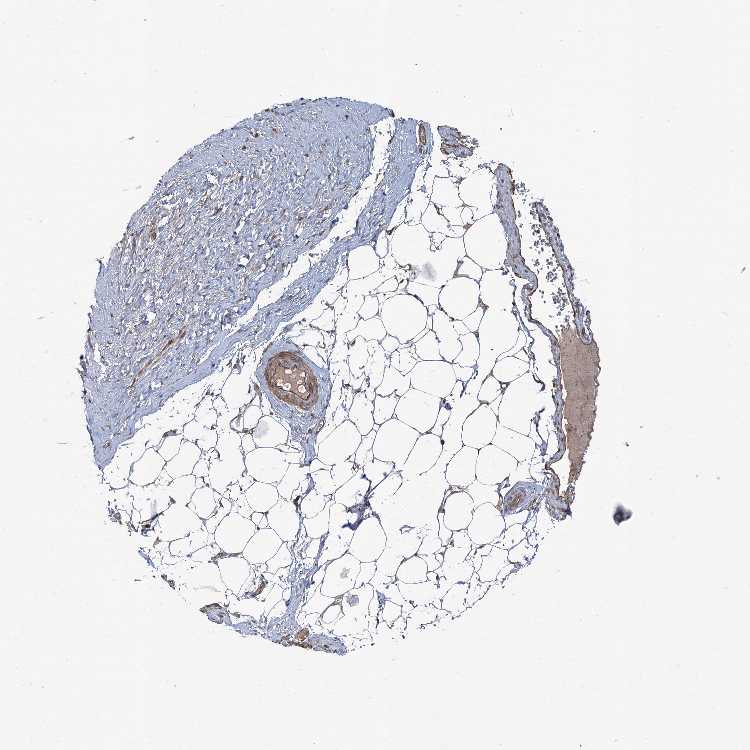

TISSUE PRIMARY DATA SOFT TISSUE Show tissue menu

SOFT TISSUE - Expression summary

SOFT TISSUE 1 - Antibody stainingi

Antibody staining in the annotated cell types in the current human tissue is reported as not detected, low, medium, or high, based on conventional immunohistochemistry profiling in selected tissues. This score is based on the combination of the staining intensity and fraction of stained cells.

Each image is clickable and will lead to virtual microscopy that enables deeper exploration of all samples and also displays staining intensity scores, fraction scores and subcellular localization as well as patient and tissue information for each sample.

Antibody HPA038313Antibody HPA038314

Fibroblasts MediumNot detected

Peripheral nerve HighMedium

SOFT TISSUE 2 - Antibody stainingi

Chondrocytes MediumLow